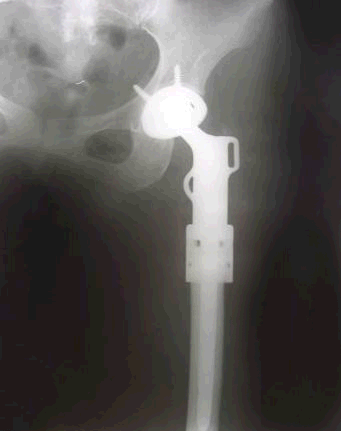

5.病例5:女 48岁, 左股骨近端骨巨细胞瘤(Campanacci Ⅲ级),行瘤段广泛切除定制型人工关节置换术

图 17 术前X线片

图 18 术后X线片